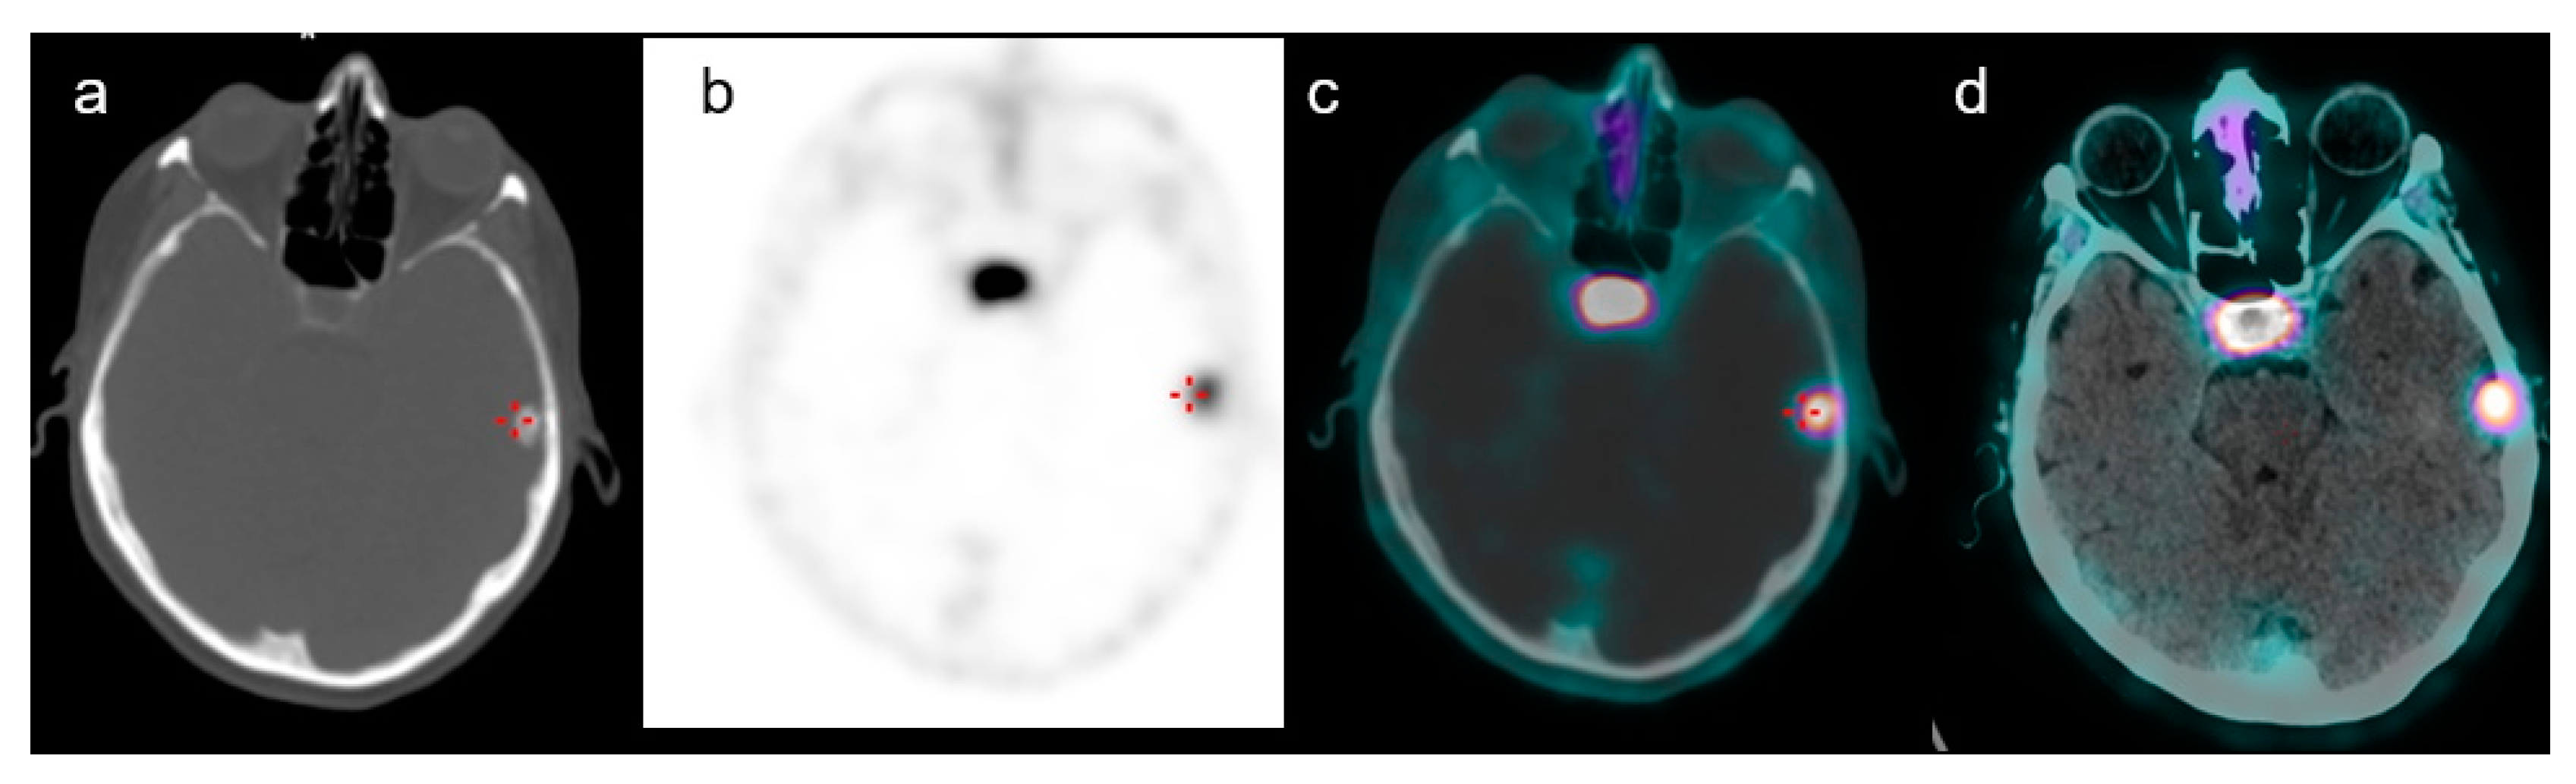

| Lesion size (mm) | 15 ± 6 (7–30) | |

| Multifocal brain uptakes | 4 (11%) | |

| Location | ||

| Right frontal region | 9 (21%) | |

| Left frontal region | 7 (17%) | |

| Right temporal region | 6 (15%) | |

| Left temporal region | 7 (17%) | |

| Right parietal region | 5 (12%) | |

| Left parietal region | 5 (12%) | |

| Left cerebellum | 1 (2%) | |

| Right cerebellum | 1 (2%) | |

| Left parasellar region | 1 (2%) | |

| SUVmax | 16.5 ± 3.7 (5–33) | |

| Lesion to brain SUVmax ratio | 351 ± 198 (80–550) |